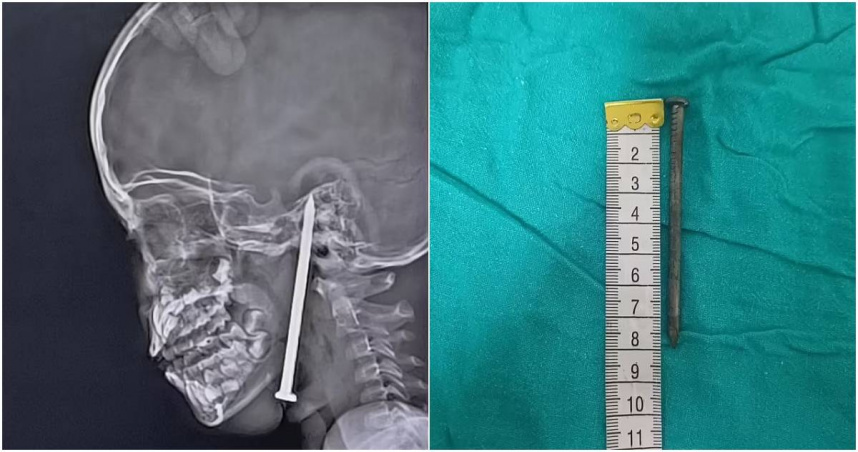

近日,印度北方邦伯爾拉姆布爾縣一名7歲男童玩耍時不慎跌倒,導致一根3英吋(約7.62公分)的鐵釘從頸部直刺入腦。(圖/翻攝X)

近日,印度北方邦伯爾拉姆布爾縣(Balrampur)發生一起意外事故,一名7歲男童玩耍時不慎跌倒,導致一根3英吋(約7.62公分)的鐵釘從頸部直刺入腦。事後,他被緊急送往印度頂尖的醫學中心喬治國王醫科大學(King George's Medical University, KGMU)創傷中心進行手術,所幸鐵釘並未傷及重要血管,最終這名男童在醫療人員的全力搶救下保住了性命。

醫療團隊在進行了核磁共振(MRI)和電腦斷層掃描(CT)檢查後發現,這根鐵釘從男童頸部下端及下顎刺入,一路向上釘至頭部,略微刺入顱骨,尖端極為接近腦部組織。但幸運的是,這根鐵釘以毫釐之差避開了主要血管以及腦部組織,因此男孩還有機會搶回一命。

在用先進的顯微外科技術和神經導航技術、歷經了4個小時的複查手術之後,醫療團隊最終成功取出了這根鐵釘,而這名男童也被轉入兒童重症觀察病房進行後續觀察治療。院方指出,目前這名男童的生命跡象穩定,預計在病房休養康復後,就可順利出院。